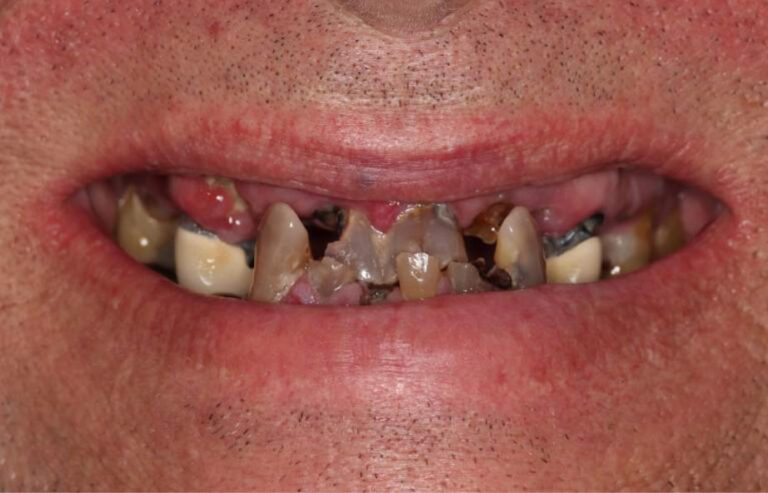

Consultation & 3D Scan

We begin with a comprehensive clinical evaluation and advanced 3D imaging to assess bone quality, anatomy, and functional needs. This allows us to design a fully customized treatment plan from day one.